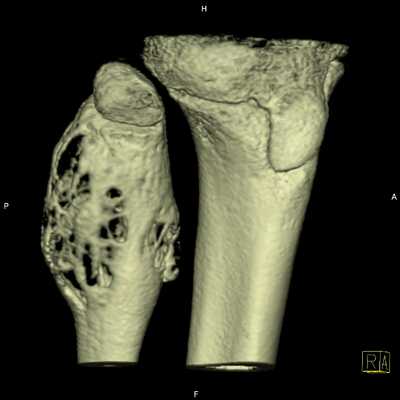

Наиболее часто аневризмальные костные кисты располагаются в губчатых костях (позвонки, кости таза, коленный сустав). Первые симптомы - скованность, дискомфорт, незначительная боль в поражённом сегменте при движении. После прекращения нагрузки симптомы исчезают. Со временем боль нарастает и становится постоянной. Дальнейшие проявления зависят от локализации аневризмальной кисты кости.

При локализации аневризмальной кисты в метафизах длинных трубчатых костей одновременно с болью появляется припухлость, болезненная при пальпации, повышение местной температуры.

Так же очень часто при аневризмальной кисте кости наблюдаются патологические переломы кости. В некоторых случаях они являются причиной выявления кист.

Аневризмальная костная киста

Встречается реже солитарной. Обычно возникает у девочек 10-15 лет. Может поражать кости таза и позвонки, реже страдают метафизы длинных трубчатых костей. В отличие от солитарной костной кисты, как правило, возникает после травмы. Формирование полости сопровождается интенсивными болями и прогрессирующим отеком пораженной области. При осмотре выявляется местная гипертермия и расширение подкожных вен. При локализации в костях нижних конечностей отмечается нарушение опоры. Заболевание нередко сопровождается развитием контрактуры близлежащего сустава. При костных кистах в позвонках появляются неврологические нарушения, обусловленные сдавление спинномозговых корешков.

Различают две формы аневризмальных костных кист: центральную и эксцентрическую. В течении болезни выделяют такие же фазы, как и при солитарных кистах. Клинические проявления достигают максимума в фазе остеолиза, постепенно уменьшаются в фазе отграничения и исчезают в фазе восстановления. На рентгенограммах в фазе остеолиза выявляется бесструктурный очаг с внекостным и внутрикостным компонентом, при эксцентричных кистах внекостная часть по размеру превышает внутрикостную. Надкостница всегда сохранена. В фазе отграничения между внутрикостной зоной и здоровой костью образуется участок склероза, а внекостная зона уплотняется и уменьшается в размере. В фазе восстановления на рентгенограммах обнаруживается участок гиперостоза или остаточная полость.